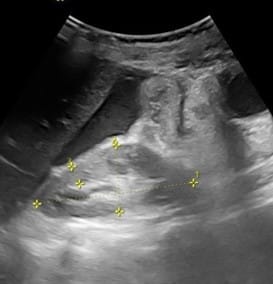

An ultrasound of the abdomen was also taken immediately after the X-ray, showing dilated bowel loops, Ascitic free fluid observed in the right iliac fossa, a Loculated collection with thick echos and echogenic lith in the appendix area, with part of the appendix visualized to be dilated, appears to be surrounded by free fluid and mesenteric inflammation. Figures 2 to 6 below show the USG images.

Figure 2: USG of abdomen showing dilated small bowel loops

Figure 3: USG of abdomen showing part of appendix- dilated, appears to be surrounded by free fluid and mesenteric inflammation

Figure 4: USG showing dilated bowel loop

Figure 5: USG showing ascitic free fluid observed in the right iliac fossa

Figure 6: USG showing loculated collection with thick echos and echogenic lith